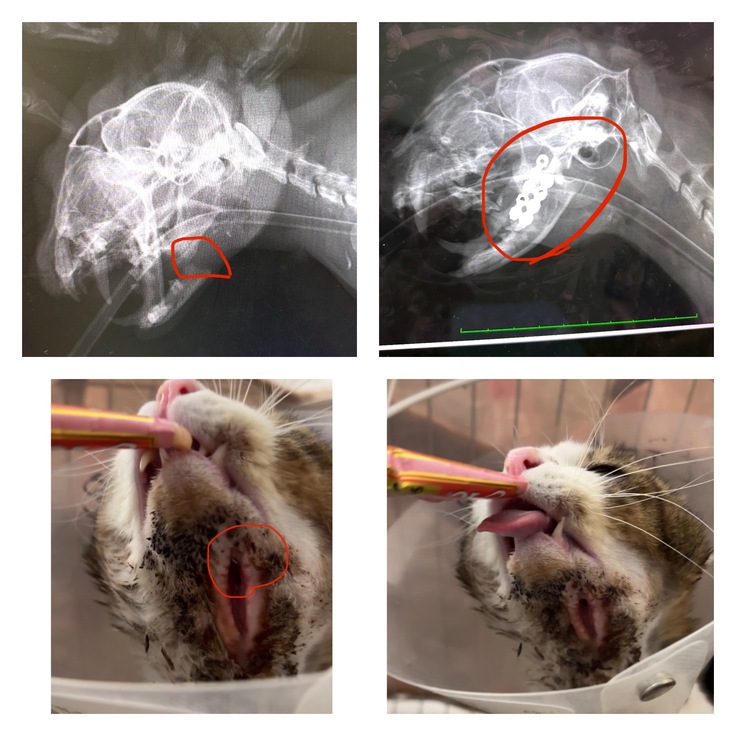

病院で捕獲器を借り、なんとかきっちゃんを捕まえて病院へ連れて行き見てもらうと、やはり顎の骨が折れていました。

しかも先生から「顎以外は怪我していないから、何か硬いもので殴られたような感じだ」と言われ、涙がこぼれました。

手術は無事に成功したのですがボルトを顎の下のからいらるのですが、顎下の皮膚は薄いので縫うことが出来ない、、勝手に皮膚が張り付いてくれるのを待つしか難しい。と言われました。

エリザベスカラーを4ヶ月間つけなければならず、金属が見えている状態は痛々しかったです。

【下記、傷口の写真なので苦手な方は控えて下さい(>人<;)】

ストレスで身体にハゲができたり、おしっこの失敗が続いたりもしました。2ヶ月たったぐらいでエリザベスカラーは小さいものに変えてみてもよいとの事だったので、柔らかいのが良さそうだなと思い購入したのですがひっくり返ってしまい1週間ぐらいでまた普通のカラーになりました。笑✨顎のズレはどうしても治らずベロが出てしまいますがそれも可愛いです。